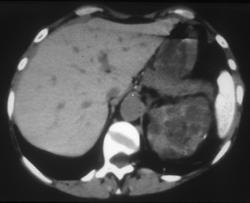

Splenic Infarction